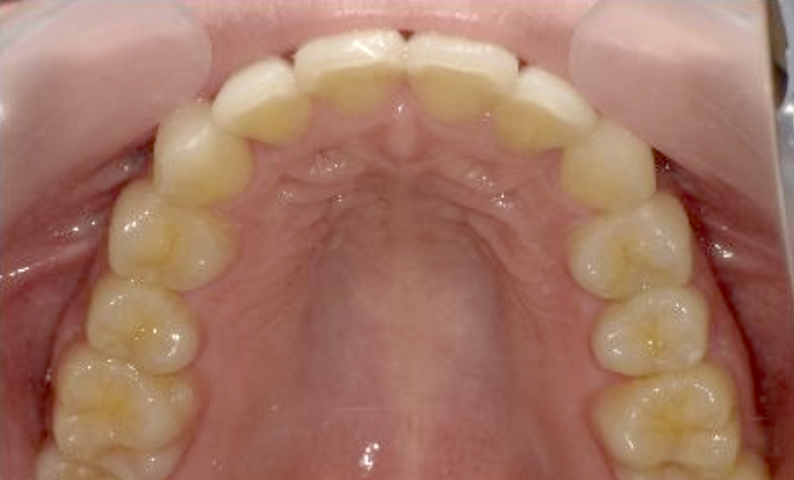

症例_024 上顎だけの部分矯正

治療期間:7ヶ月金額:30万円+税女性前歯のガタガタ上の前歯だけ

| Before | After |